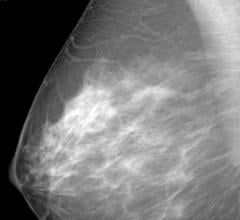

Mammography

Mammography is a breast imaging technique that uses X-rays to diagnose and locate tumors of the breasts.